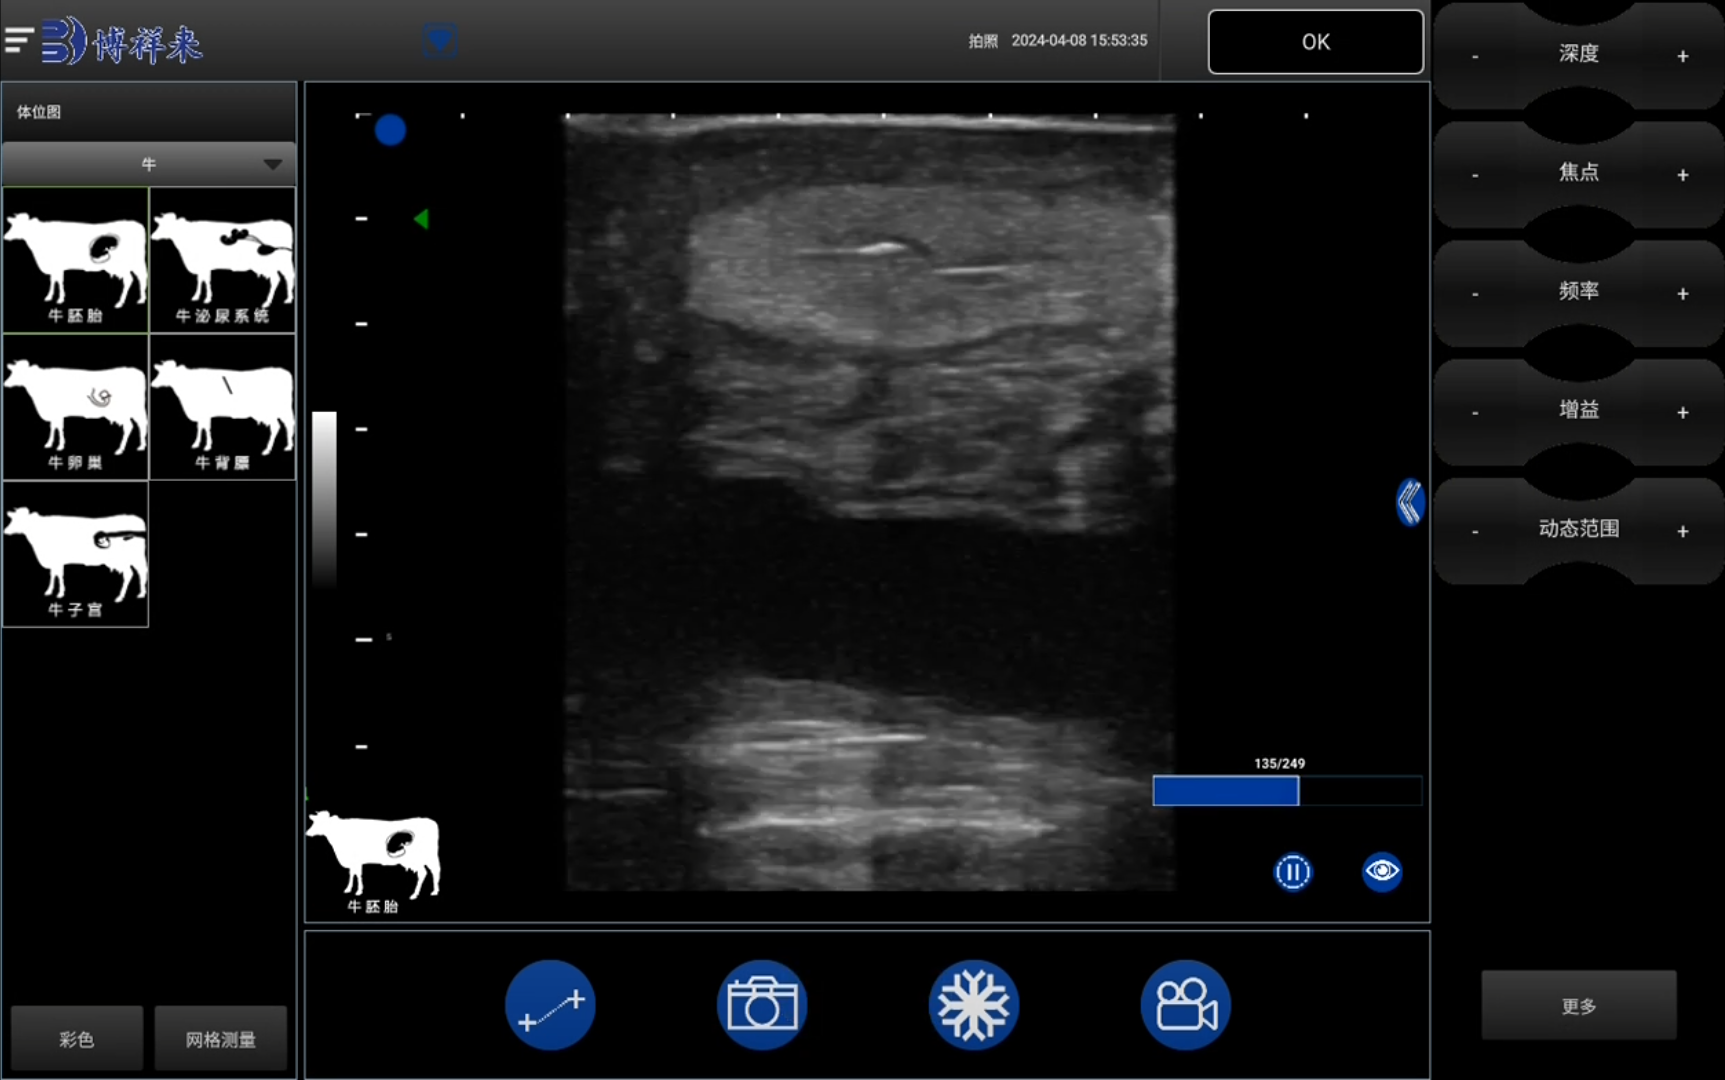

传统判断方法如触诊或行为监测往往滞后且主观性强,而使用奶牛用B超机进行影像检测,牧场管理者可以更早、更直观地掌握母牛的子宫恢复情况。通过B-模式超声扫描子宫角及子宫颈,技术员可测量子宫腔宽度、壁厚变化及内腔是否有残留液体或积物。积液或炎症若未及时被发现,会延缓子宫复旧进程,从而导致发情延迟、配种失败或空怀。

随着技术升级,智能AI奶牛B超机不仅具备清晰成像,还配备自动测量与图像标注功能,使得子宫复旧评估更加标准化。牧场技术员只需定位探头扫描子宫两角及颈部,系统便可自动识别子宫腔直径变化、判断是否存在异常液体回声,并生成检测报告。通过这种方式,牧场可以在母牛产后约三至四周时进行一次子宫复旧影像检测,及时发现潜在问题并调整配种时间,有效缩短空怀期并提升繁殖效率。